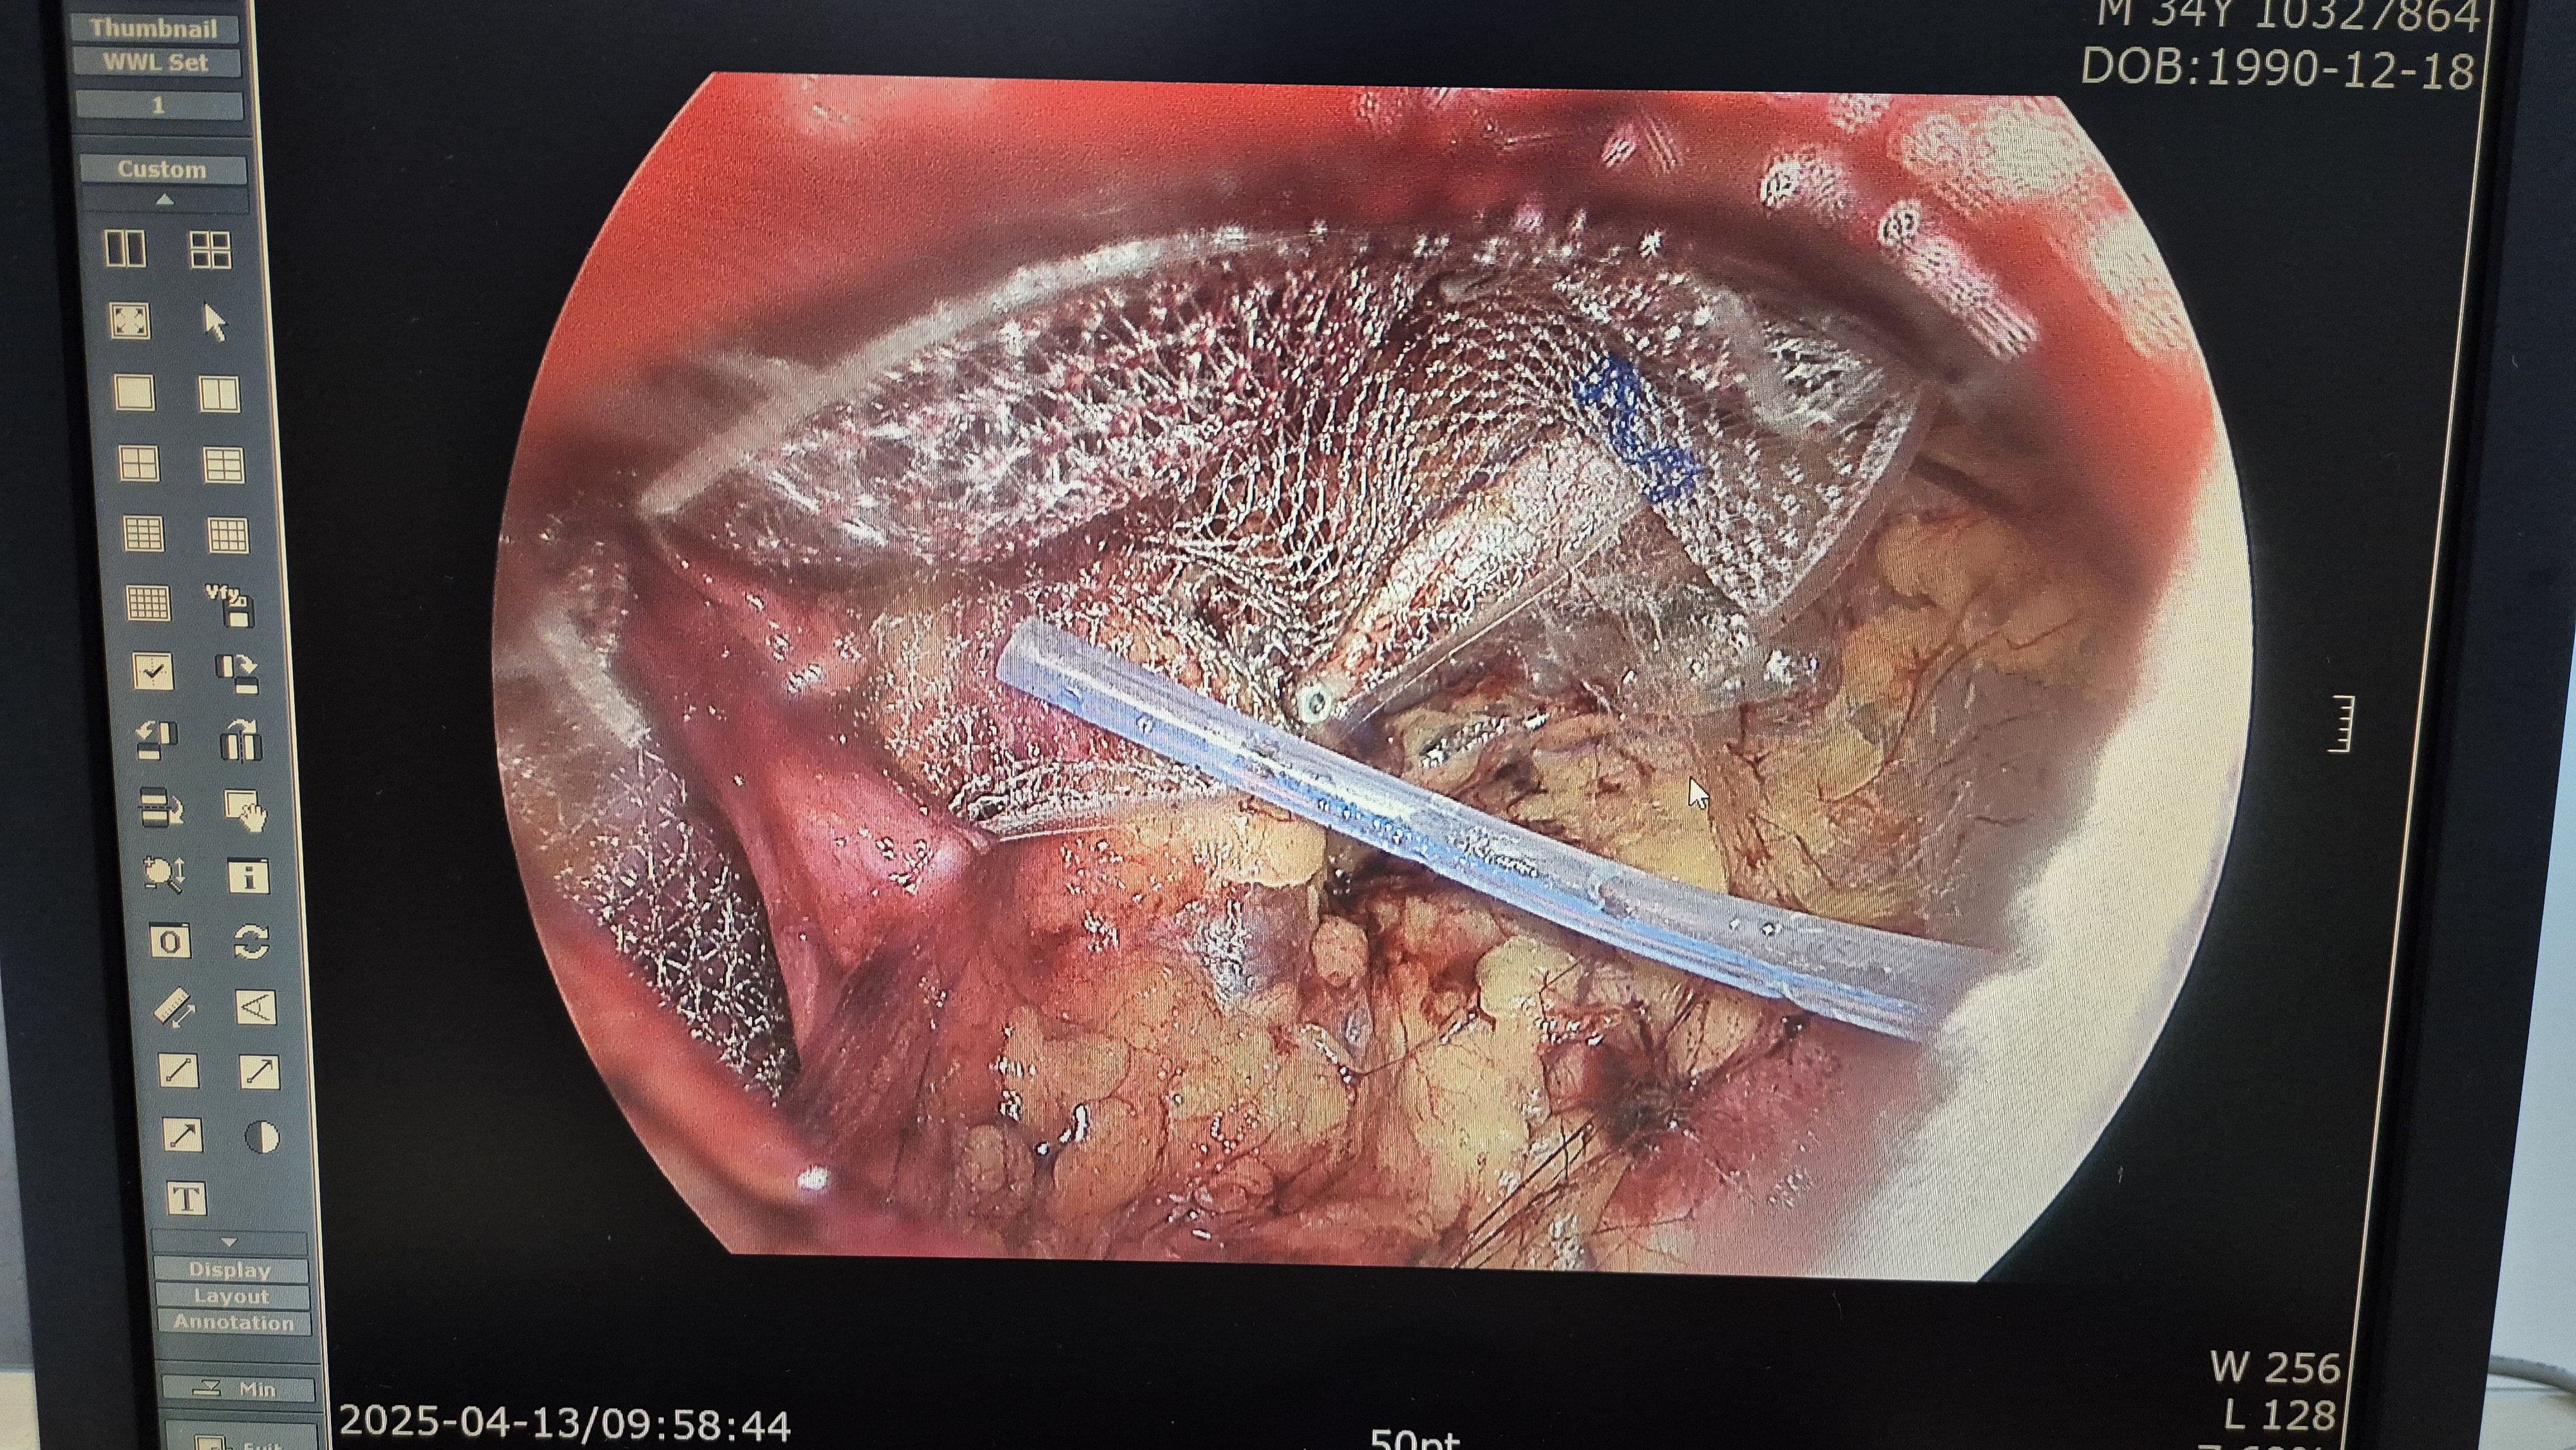

메쉬로 고정.